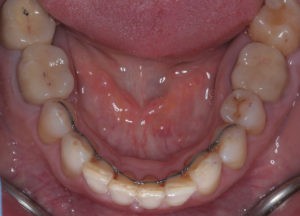

Искривление окклюзионной кривой (плоскости смыкания зубов), возникшее в результате парадонтита, успешно удалось устранить, используя накусочные брекеты на верхних резцах и микроимплант, установленный во фронтальном участке нижней челюсти:

Пациентка довольна профилем и красивой улыбкой.